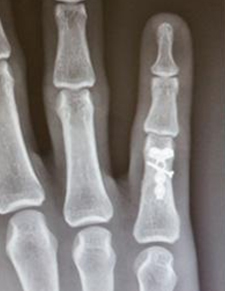

Beşinci metakarpalın boynundaki kırık, kliniğimizde çok yaygındır. Volar plaka fiksasyonu, erken mobilizasyona izin verdiği ve ekstansör tendon yapışmasını önlediği ve cerrahi yara izi yerleşiminin avuç içinde olması nedeniyle tercih ettiğimiz tedavi yöntemidir.

Uygun implantlarla sabitlenen kırıklar erken el tedavisine izin verecektir. Komplikasyonlar arasında hareketi engelleyen uzun vidalar veya teller, kırık parçalarının kötü hizalanması, tendonların sıkışmasına ve hareketi engellemesine neden olan çok büyük implantlar ve cilt ve dokuların uygunsuz yönetimi nedeniyle oluşan ciddi enfeksiyonlar yer alır. Bunlar potansiyel olarak iyileşmeyi ve işe veya spor aktivitelerine erken dönüşü yavaşlatabilir.